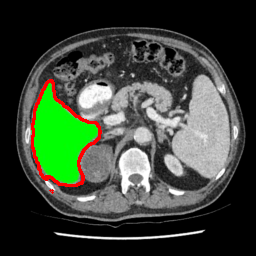

| U-Net | nnU-Net | TransU-Net | SAM-PP-0 | SAM-PP-5 |

| SAM-PP-50 | SAM-PP-100 | SAM-Mix-5 | SAM-Mix-50 | SAM-Mix-100 |

Our primary findings comparing the proposed model to baseline fully-supervised models when segmenting the liver from the LiTS dataset are reported in Table 1. The reported results demonstrate that our SAM-Mix model consistently achieves higher Dice scores compared to the fully supervised baselines as well as the two-stage SAM-PP method. Against U-Net, the best-performing fully supervised method, the SAM-Mix variant trained on 50 segmentation labeled slices (SAM-Mix-50), achieves a Dice score improvement of 5.9%. In terms of Hausdorff distance, while the fully-supervised baselines do slightly outperform SAM-Mix-5 and SAM-Mix-100, SAM-Mix-50 does achieve a lower Hausdorff distance by 22.38%. Qualitative evaluation as shown in Figs. 3 further affirms the superiority of SAM-Mix over baseline and existing fully-supervised methods as well as the two-stage SAM-PP variants. Furthermore, the boxplot visualization in Fig. 2 showcases consistently improved performance by SAM-Mix outperforming all the fully supervised and semi-supervised methods.